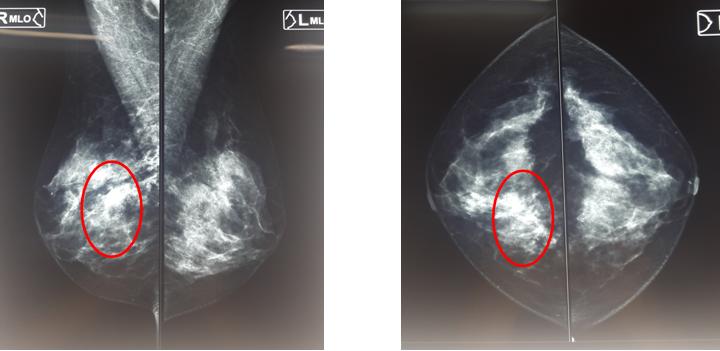

Bệnh nhân được tiến hành chụp X-quang tuyến vú (mammography):

Hình 1: Hình ảnh vi vôi hóa vị trí ¼ dưới trong vú phải (vòng tròn đỏ)

Kết quả cho thấy: Vị trí ¼ dưới trong vú phải có đám tổn thương kích thước 17x33mm, bờ và ranh giới không rõ, kèm theo có nhiều nốt vi vôi hoá dạng vô định hình (BIRADS 4b). Vú trái không phát hiện bất thường.